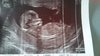

My już po badaniu. Wszystko w jak najlepszym porządku :-) :).

Cała anatomia płodu prawidłowa. Kość nosowa obecna. NT 1.3.

Dzidziolek badanie zaczal stojac na glowie... Hihi. Cudny widok. Pozniej troche spał, troche fikał :laugh2:. Moj stwierdzil ze nam nawet jezyczek pokazał... Hihi ja nie widziałam ;).

Termin wg usg 26.12 świąteczny prezent :-) :)!

Dr stwierdzil ze na określenie plci jeszcze za wcześnie...